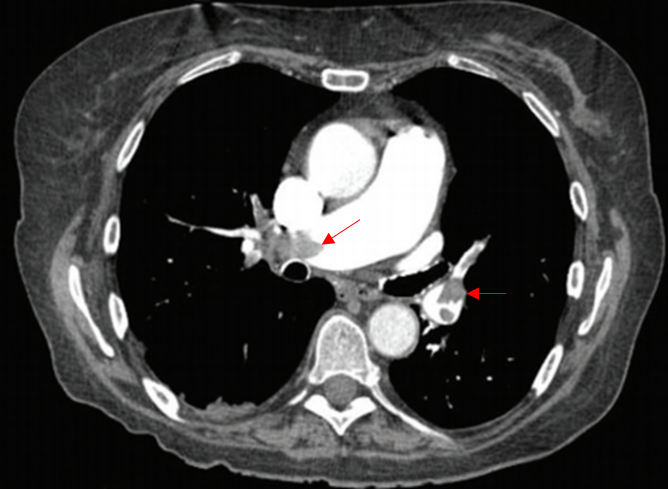

78세 남자가 2일 전부터 숨이 찬다며 응급실에 왔다. 1주 전 오른쪽 넙다리뼈 골절 수술을 받은 후 누워 지냈다고 한다. 혈압 80/56 mmHg, 맥박 110회/분, 호흡 20회/분, 체온 36.6°C이다. 가슴 청진에서 심음은 빠르고 복장뼈 왼쪽 옆 네 번째 갈비사이 공간에서 3/6도의 수축기 잡음이 들린다. 호흡음은 정상이다. 오른쪽 종아리가 부어 있다. 가슴 컴퓨터단층촬영사진이다. 적합한 치료를 고르시오 (두 가지).

Img | CT: 양측 폐동맥 혈전 |

• CT에서 폐동맥 혈전이 보이므로 폐색전증으로 진단할 수 있다.